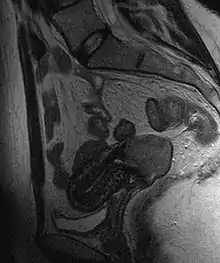

Cervical cancer seen on a T2-weighted sagittal MR image of the pelvis

Often before the biopsy, the doctor asks for medical imaging to rule out other causes of woman's symptoms. Imaging modalities such as ultrasound, CT scan, and MRI have been used to look for alternating disease, spread of the tumor, and effect on adjacent structures. Typically, they appear as heterogeneous mass on the cervix.[53]